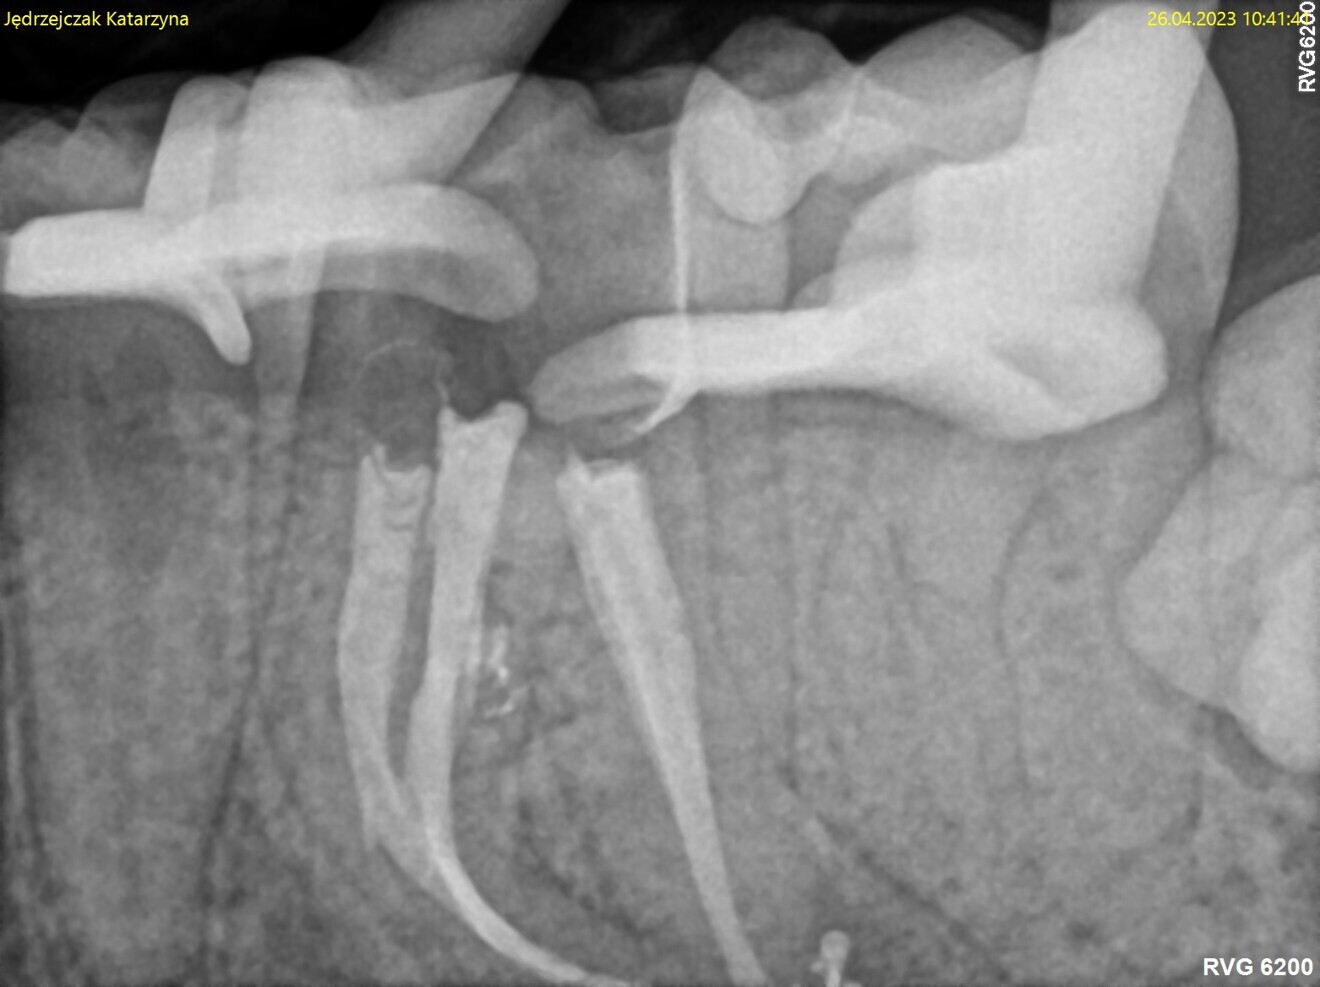

Fig. 1: Pre-op radiograph. Periapical lesion and broken file visible.

The periapical radiograph and the CBCT scan revealed that the file had broken far beyond the curvature in the mesiobuccal canal and below the junction with the mesiolingual canal. Also, a periapical lesion was visible around the apices of the mesial and distal roots (Figs. 1–3). The length of the file was approximately 5 mm. Bypassing the file through the mesiolingual canal would have been a risky procedure because it may have caused the fracture of the second instrument and the obturation may also have been very challenging. Thanks to SWEEPS technology and a bioceramic sealer, an alternative approach could be taken. After administering anaesthesia and placing a dental dam, the temporary restoration was removed (Figs. 4 & 5). The pulp chamber was rinsed with 5.25% sodium hypochlorite and the irrigant activated with ultrasonics. After cleaning the chamber of the tooth, the dental dam and clamp were rinsed with water and dried and flowable dental dam was placed to seal the tooth and enlarge the space in the pulp chamber for the laser-activated irrigation (Fig. 6). Activation was performed with the SkyPulse laser (Fotona). The AutoSWEEPS mode was chosen. The power of activation was set to 1 W. The flat SWEEPS 300/20 fibre tip was used (Fig. 7). The tip was placed slightly below the orifice of the mesiobuccal canal for the majority of the irrigation with sodium hypochlorite. After 120 seconds of activation with sodium hypochlorite, the tip was placed in the pulp chamber to activate the sodium hypochlorite in all the canals simultaneously for 30 seconds. This procedure was continued for 30 minutes. Only the distal canal was shaped with rotary files, up to size 40/.04. Both mesial canals remained the same size as they were before the file broke during the primary treatment. Finally, the canals were flushed with EDTA activated with AutoSWEEPS at a power of 0.4 W, and sodium hypochlorite was activated for three cycles with AutoSWEEPS at a power of 0.6 W and with a 30-second break for the resting phase. The irrigant flow between the mesiobuccal and mesiolingual canals was rapid, indicating that obturation could be performed.